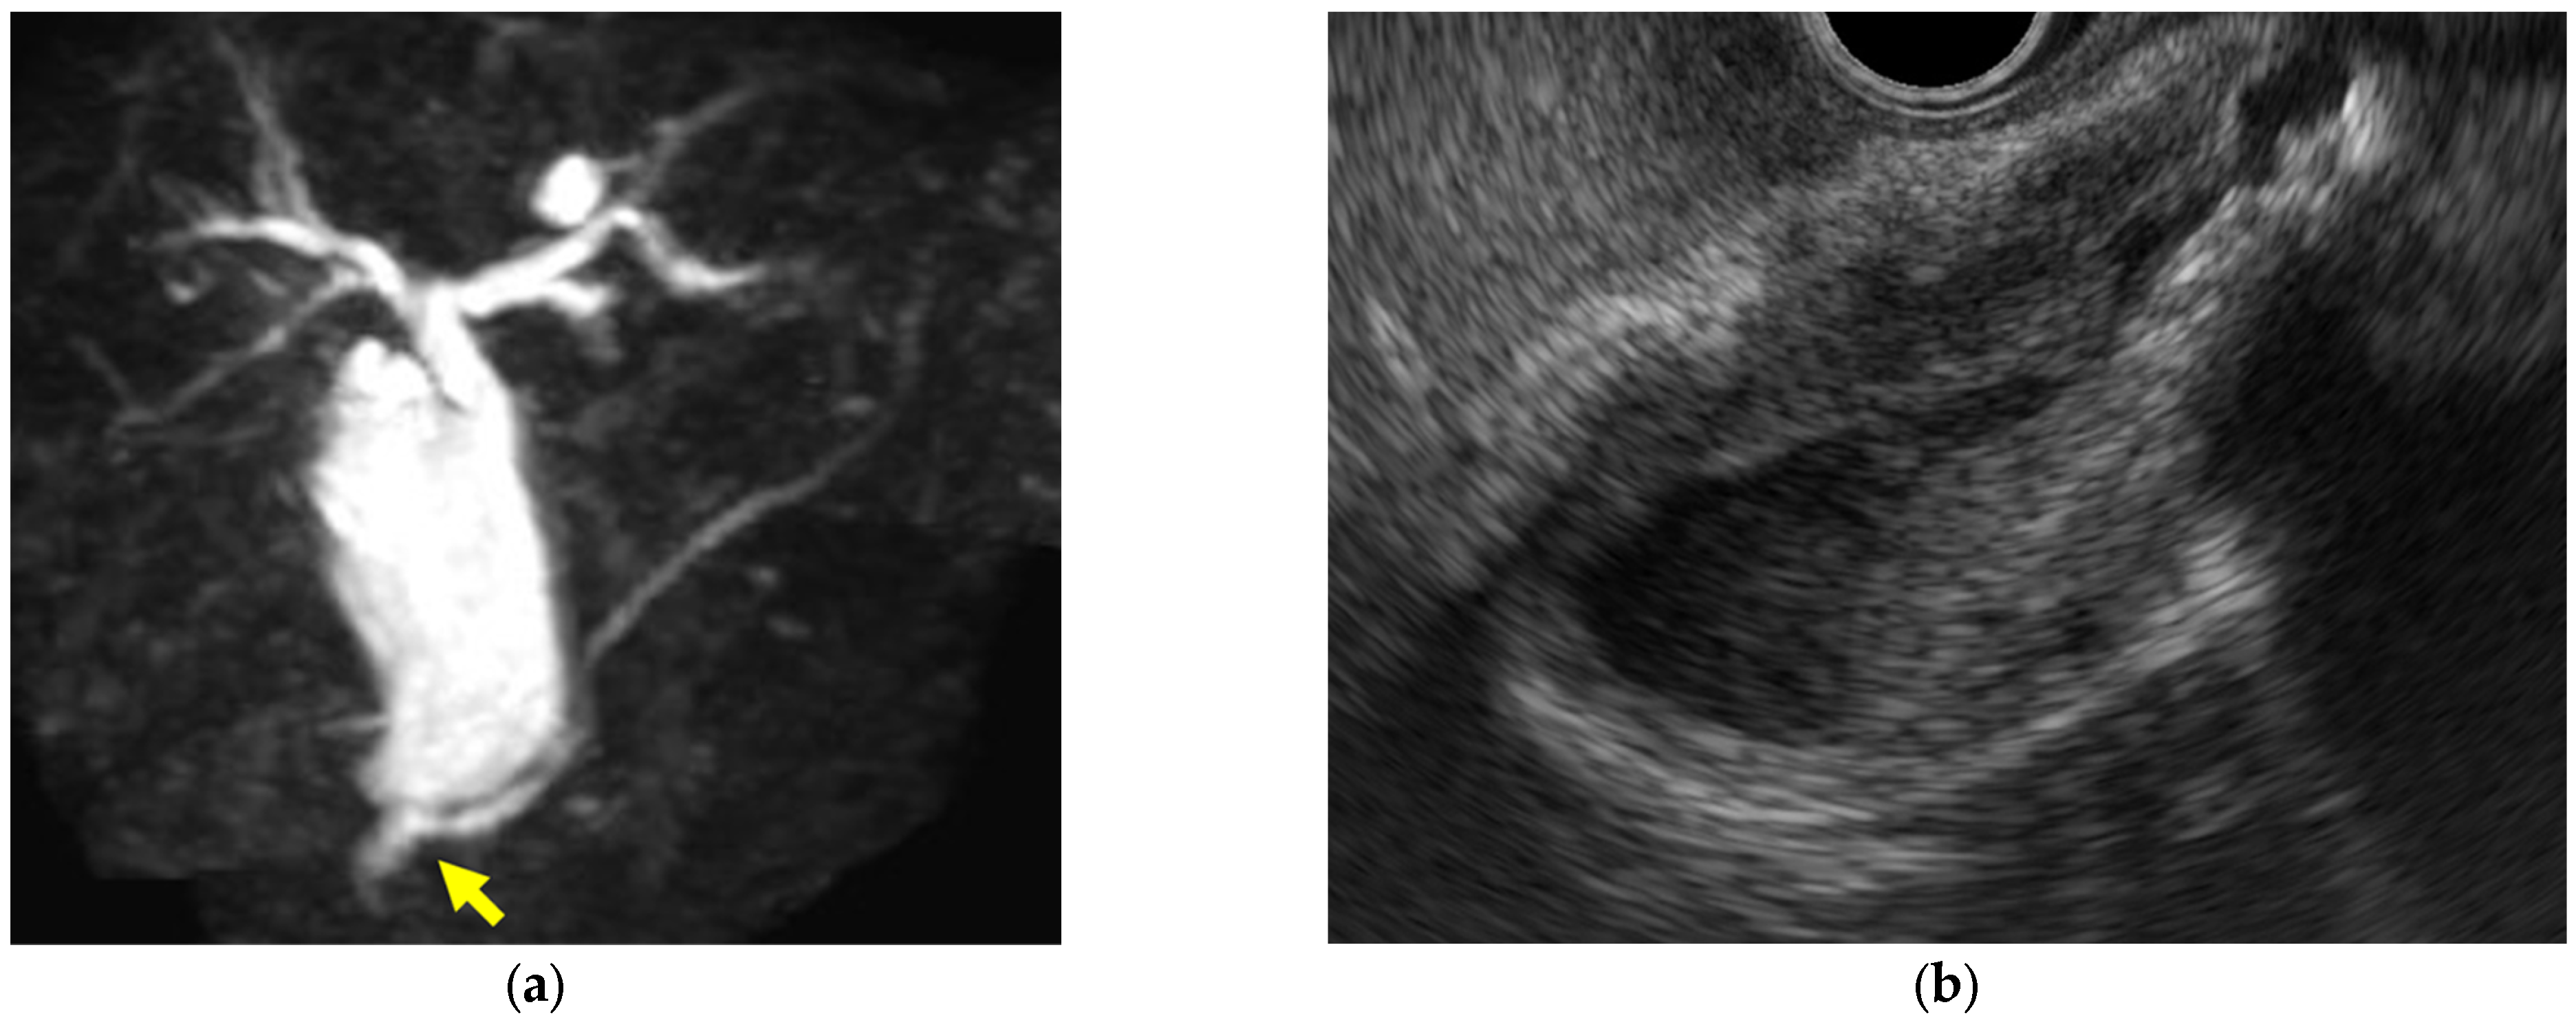

- Immunoglobulin G4-related sclerosing cholecystitis (IgG4-CC) (Figure 3)

| Immunoglobulin G4-related sclerosing cholecystitis | Smooth | No distinctive findings | Preserved |